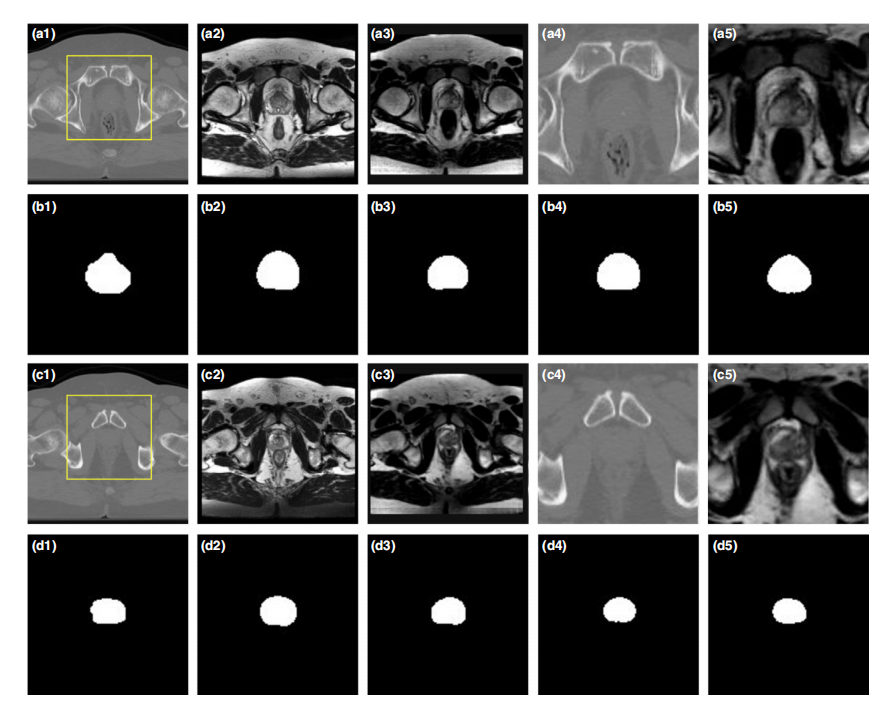

FIG. 5. Comparative analysis between the proposed method and existing U-Net models demonstrates a comprehensive assessment of various imaging techniques._ (a1) and (c1) depict the computed tomography (CT) images, while (a2) and (c2) illustrate the magnetic resonance imaging (MRI). The synthetic MRI (sMRI) results are shown in both (a3)-(c3). Additionally, zoomed-in regions are provided for each modality: CT scans in (a4, c4) and sMRI scans in (a5, c5_). The segmented contours obtained from each model are displayed across all modalities, including manual contours (b1–b5), CT U-Net (b6), sMRI U-Net (b7), CT deep attention fully convolution network (DAFCN, b8_), and sMRI DAFCN (b9)._

图5. 展示了所提出方法与最新U-Net模型在医学图像分割方面的对比实验。(a组和c组分别展示了CT图像的原始结果。(b组和d组则展示了 MRI 的原始图像。(c 组展示的是合成 MRI (s MRI ) 的结果。e 组展示的是 a 组矩形框内 CT 图像的放大效果。(f 组展示的是 c 组矩形框内 s MRI 图像的放大效果.b 组到 b 五分别展示了手动轮廓二值掩膜的效果.d 组到 d 五则展现了各分割算法的具体表现.]